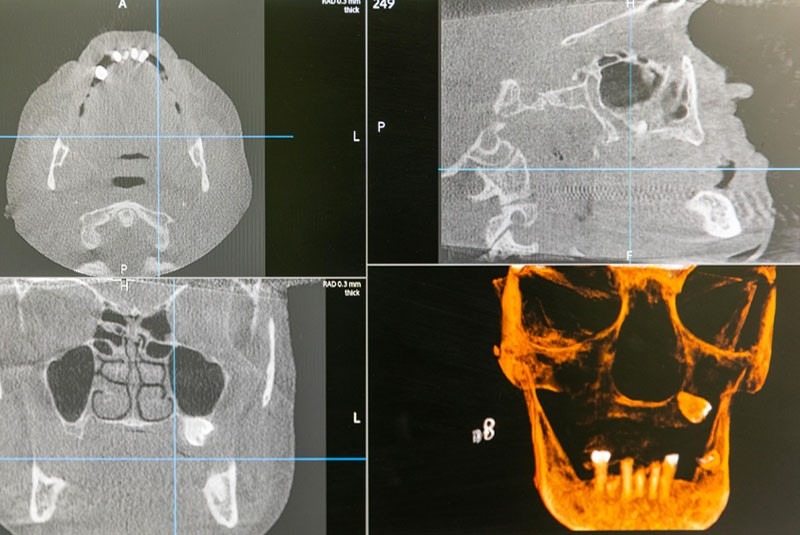

Digital Diagnostics For Predictable Planning

The best dental implant outcomes start with the best diagnostics. Our 3D Cone Beam CT scanner produces detailed, highly accurate computer models of your anatomy, including your teeth, bone volume, jaw joints, and surrounding structures. Placing implants appropriately determines their stability and longevity. Rather than depending on old-fashioned x-rays, the precision measurements collected with the CBCT allow us to explore your case from every angle and craft your treatment plan to ensure ideal implant placement with no surprises.